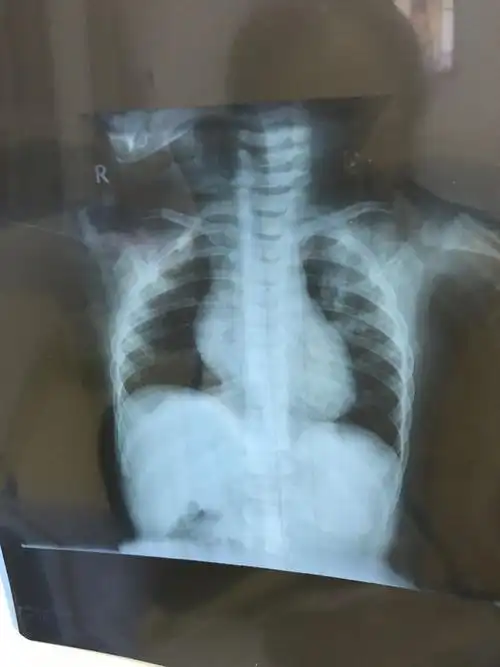

新生儿30天得肺炎,现在在妇幼icu,这是胸片,很严重吗

胸片可见两肺弥漫炎性渗出影,因此诊断为小儿支气管肺炎

用了退热贴,就降下来了,第二天去医院,拍的胸片医生说严重支气管肺炎

请各位大夫帮看看,孩子这个胸片正常了吗?还需要继续吃药吗?